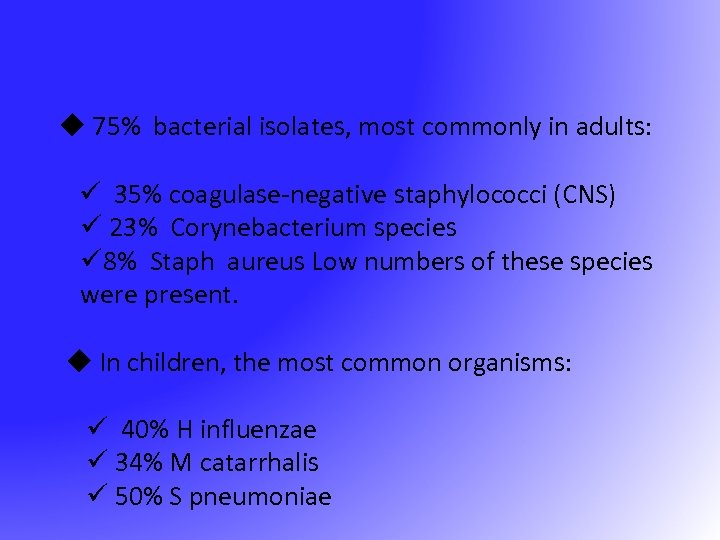

u 75% bacterial isolates, most commonly in adults: ü 35% coagulase-negative staphylococci (CNS) ü 23% Corynebacterium species ü 8% Staph aureus Low numbers of these species were present. u In children, the most common organisms: ü 40% H influenzae ü 34% M catarrhalis ü 50% S pneumoniae

u 75% bacterial isolates, most commonly in adults: ü 35% coagulase-negative staphylococci (CNS) ü 23% Corynebacterium species ü 8% Staph aureus Low numbers of these species were present. u In children, the most common organisms: ü 40% H influenzae ü 34% M catarrhalis ü 50% S pneumoniae